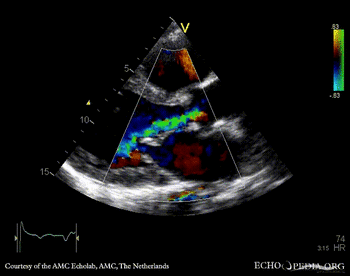

E00439.gif

A4CH: Color Doppler, severe tricuspid regurgitation Continuous-wave signal of tricuspid regurgitation, increased systolic pulmonary artery pressure